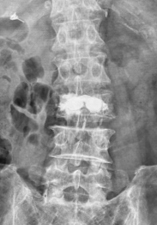

椎体形成術(VP、BKP、VBS)および後方・後側方固定術

対象となる疾患:脊椎圧迫骨折や転移性脊椎腫瘍による病的骨折など

椎体形成術でセメントや人工骨を注入して、骨折を人工的に接合します。椎体形成術のみでは固定性が弱い場合や骨脆弱性が強い場合には、スクリューなどを用いて脊椎を安定化させます。原則、手術翌日より軟性もしくは硬性のコルセットを装着し、起立・歩行を開始します。

(左)第12胸椎および第1腰椎の骨粗鬆症性椎体骨折を認めます。(中)MRIでは第1腰椎に大きな骨欠損を認め、骨折が難治性で不安定であることを示しています。(右)第1腰椎に椎体形成術を施行し、さらに骨が脆かったため、頭尾側にスクリューを挿入して固定しています。